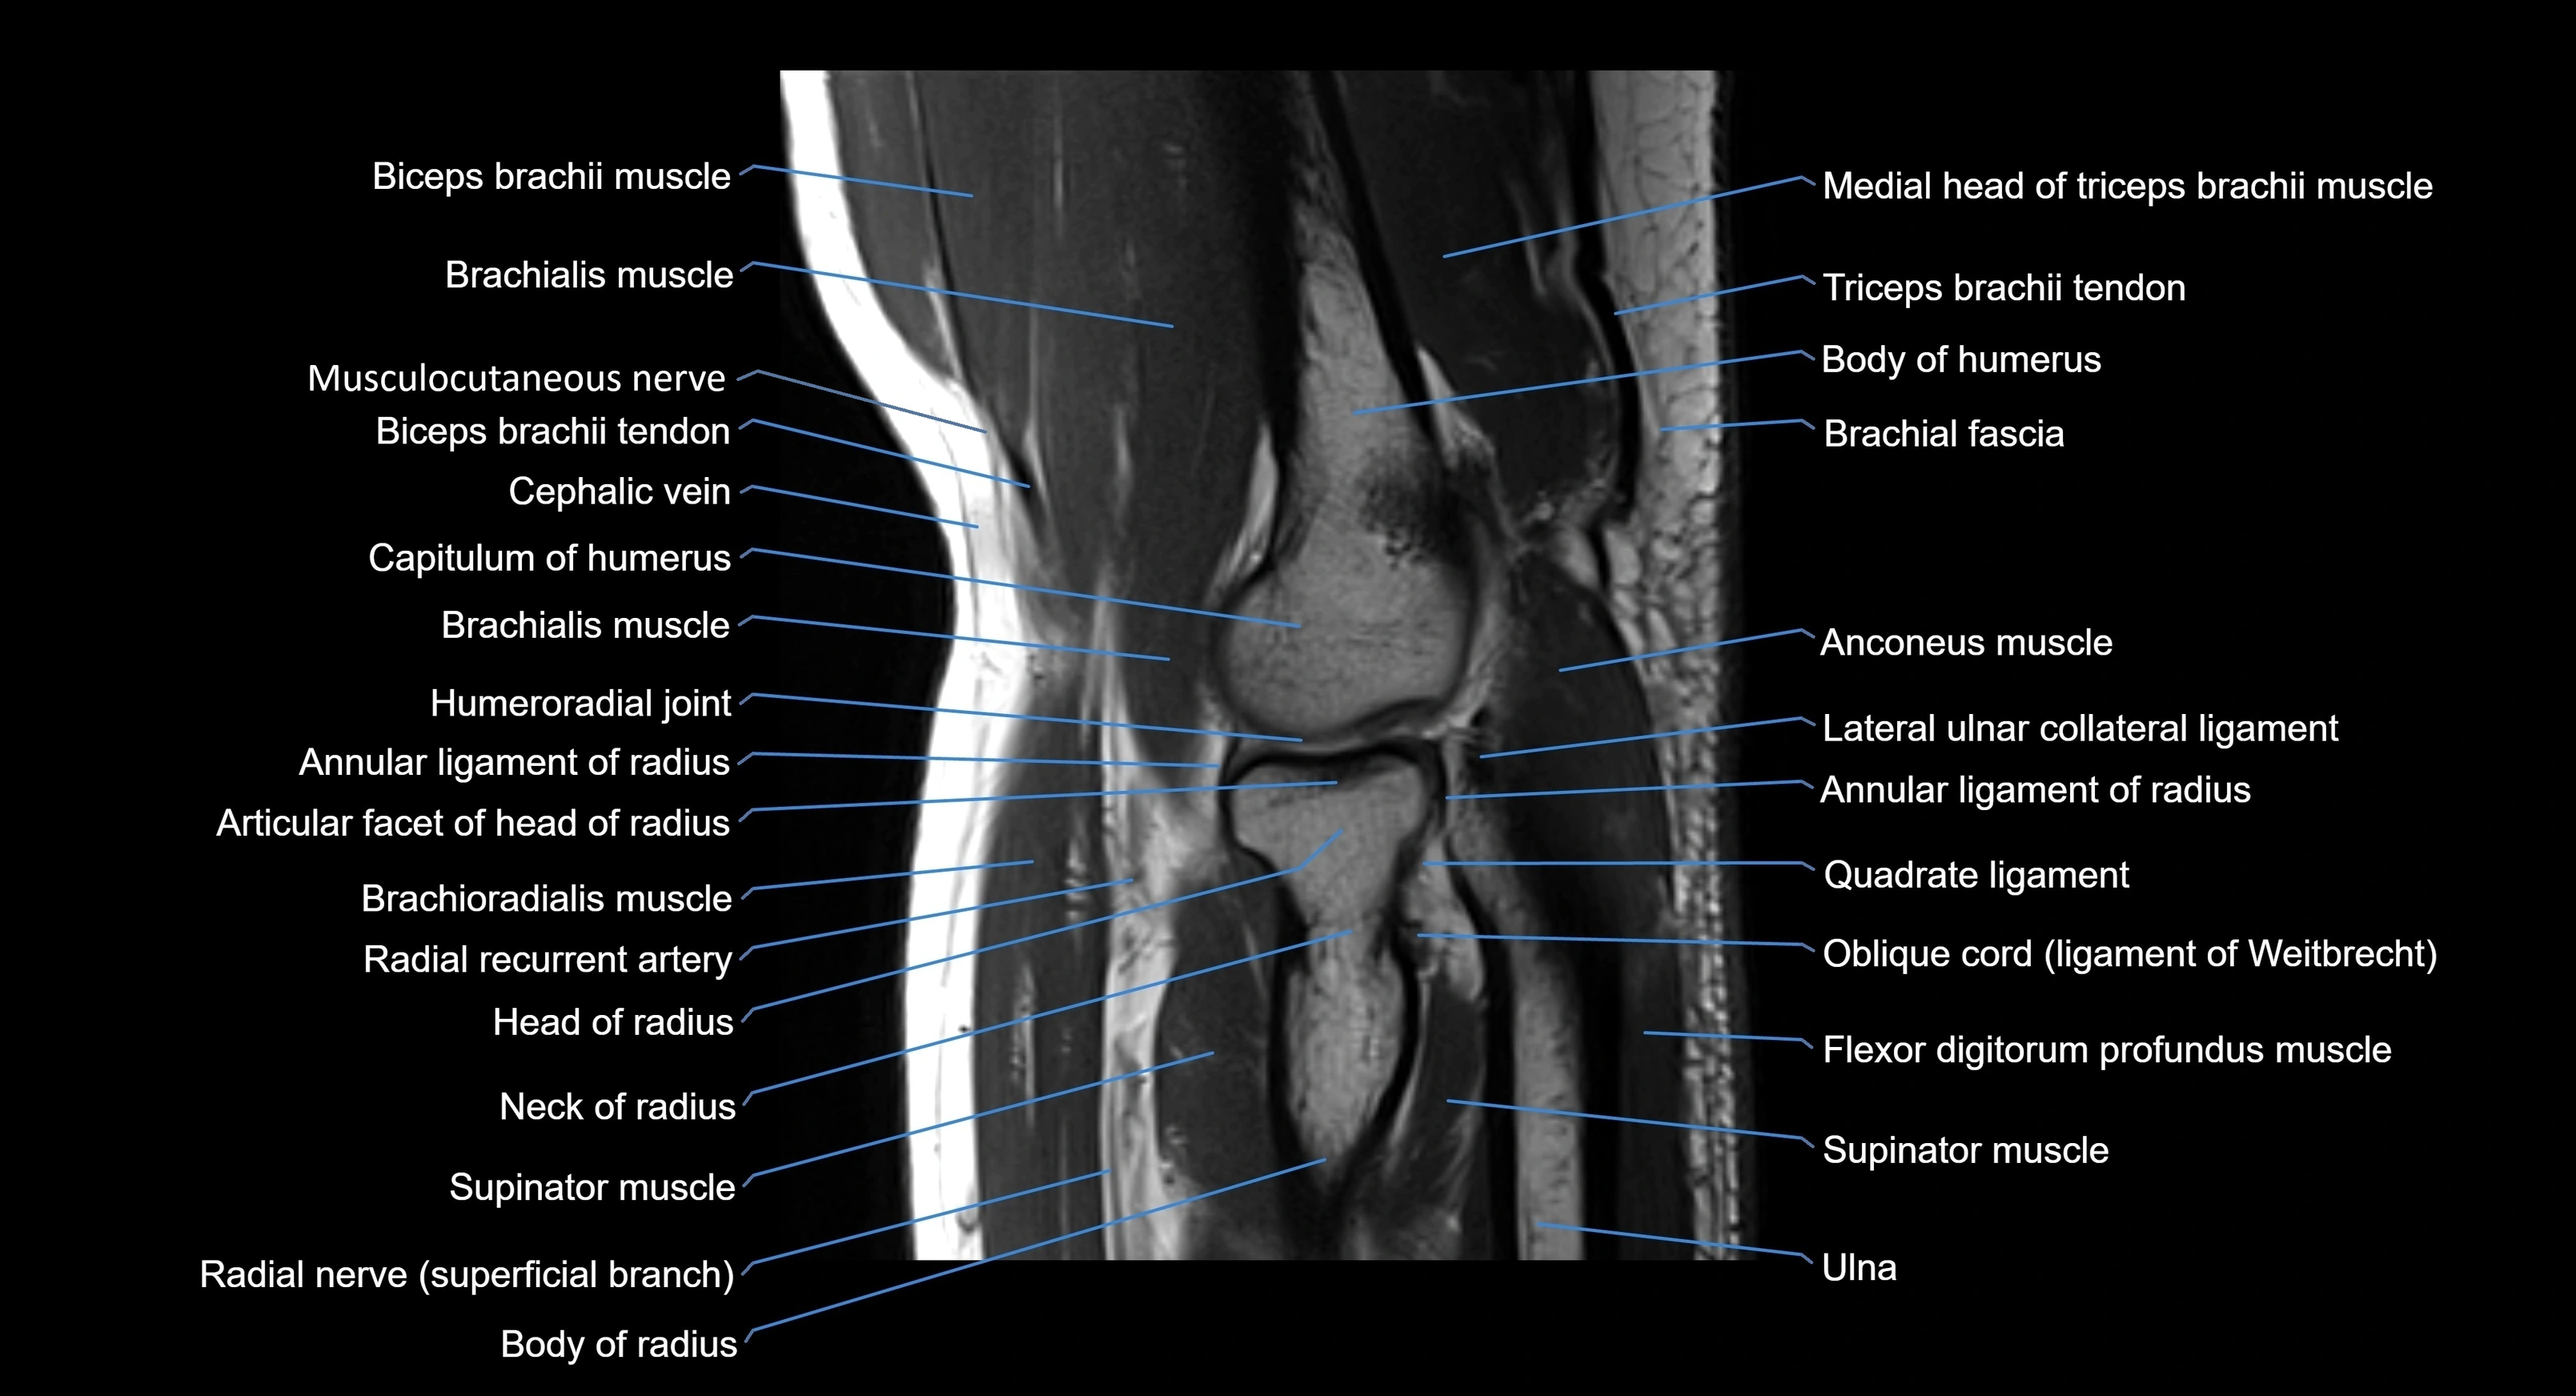

MRI image

image